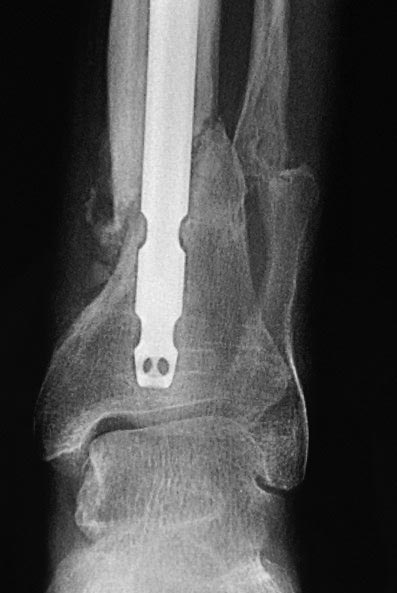

Уважаемые коллеги выразите Ваше мнение по следующему случаю. Молодой

человек, 27 лет, находится на лечении с диагнозом: Ложный сустав

большеберцовой кости в нижней трети, фиксированный интрамедуллярным

блокированным стержнем (12.02.2014 г), ложный сустав малоберцовой кости

в нижней трети левой голени, посттравматический артроз левого

голеностопного сустава 1 стадии. Укорочение левой нижней конечности на

В феврале 2014 г выполнил первым этапом: Фиксацию ложного

сустава в АНФ с восстановлением осей сегментов. Через семь дней БИОС с

рассверливанием.

После операции - вальгус голеностопного сустава. Гладкое течение

Через 6 мес. контроль - линия ложного сустава прослеживается, но имеется

периостальная костная мозоль.

Не хватает стабильности.